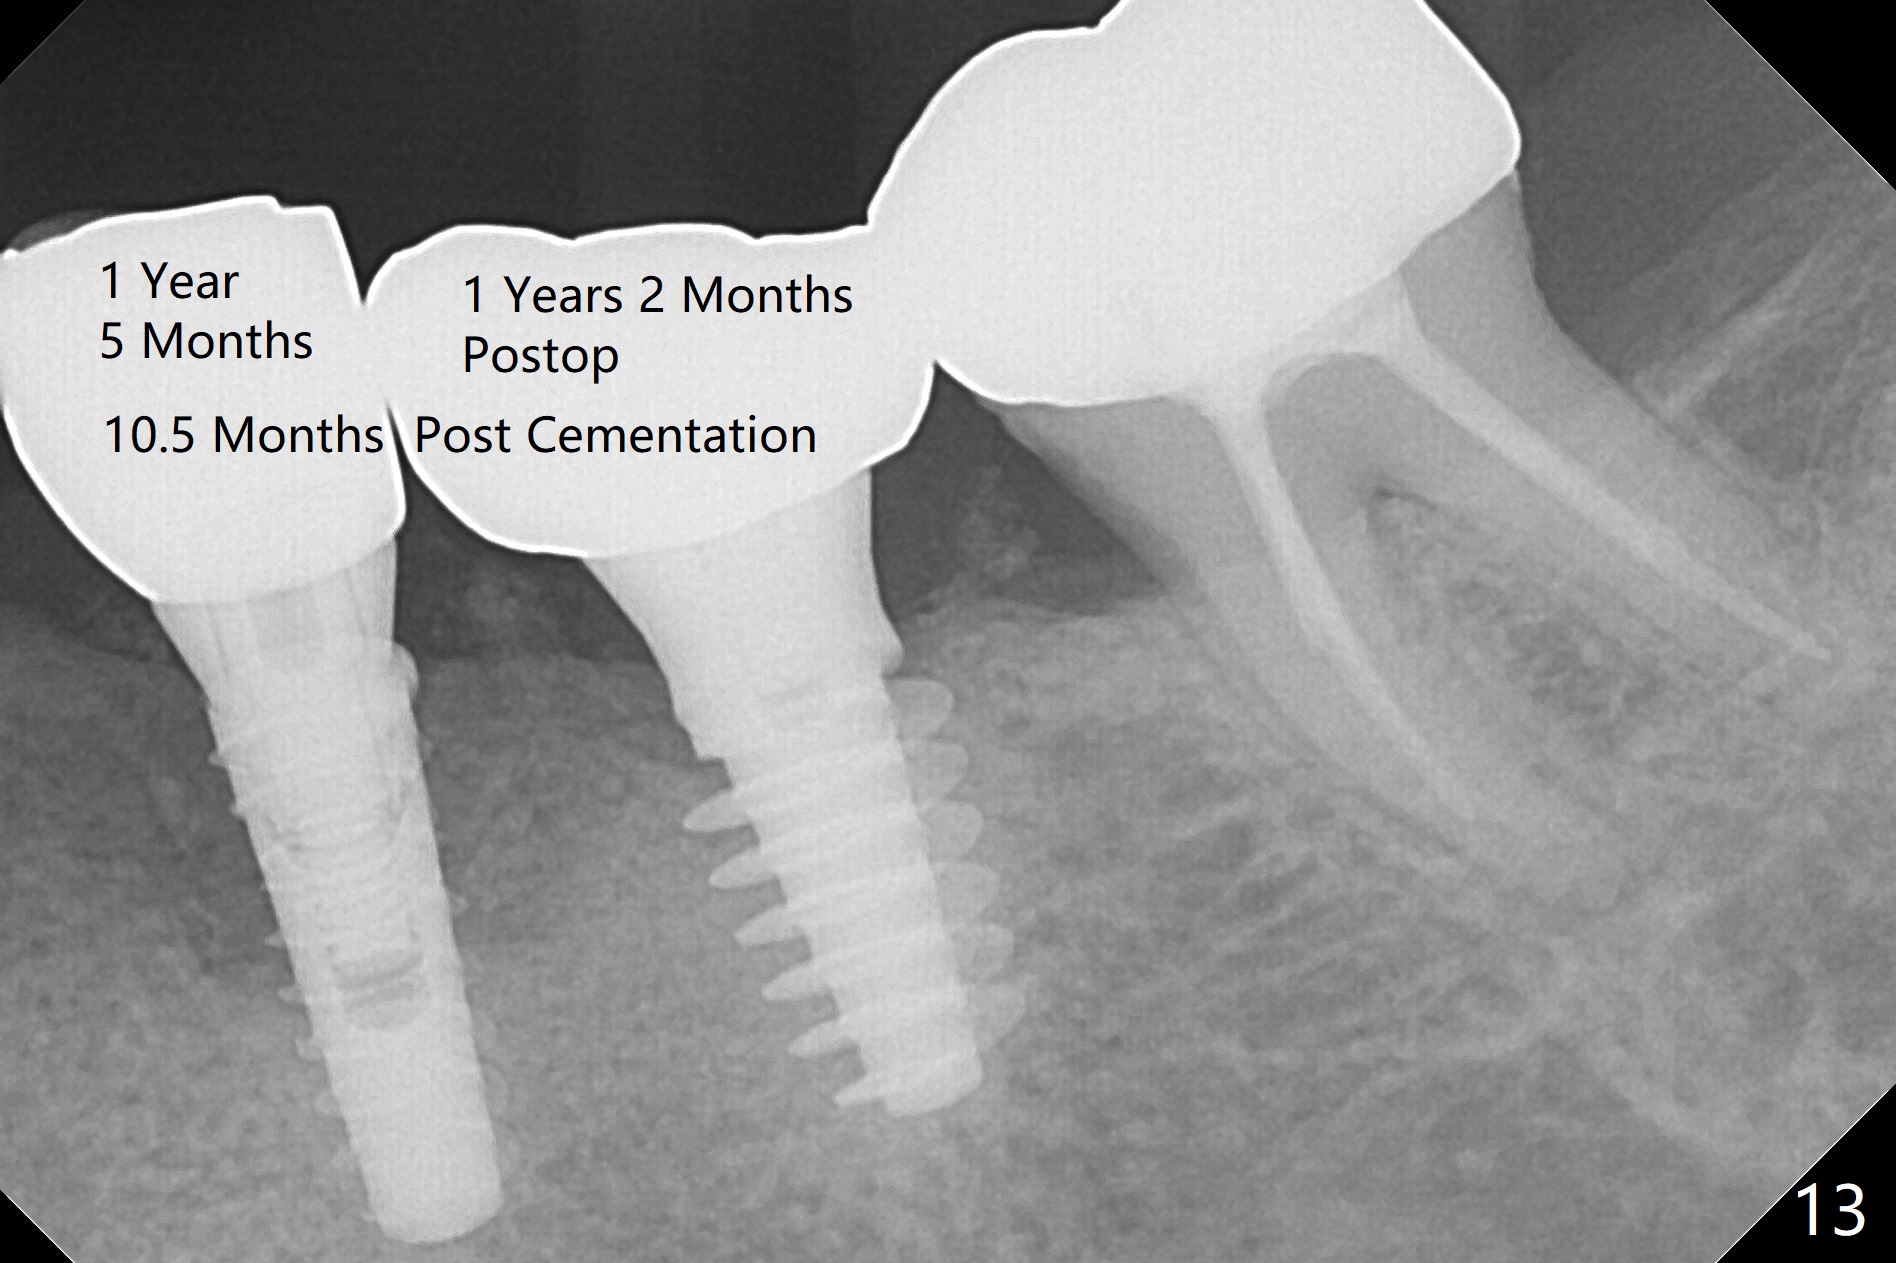

There is no bone loss at #20 or 19 six and 3 months postop, respectively (Fig.6,7). After placing and trimming a 4.3x3 mm Magicore solid abutment, impression is taken (Fig.8). After cementation for #19 and 20 crowns, the crown of #20 is removed for cement removal; attention is paid to cement removal around the crown at #19. In fact, the removal is ineffective with the crown of #20 is reseated and retightened (Fig.9 >). Repeated removal proves to be futile (Fig.10 >). The most effective method will be to take X-ray immediately after #20 crown removal and reseating without torque so that it will be easier to remove the remaining cement if needed. It may be ok in term of hygiene, since proximal brush is used daily. While the crowns at #18 and 19 are being redone because of food impaction, the tooth #18 needs RCT; the Magicore seems to have no bone loss 4 months post cementation (Fig.11). CBCT shows that the Magicore seems to have been placed in the middle of the crest 7 months post cementation (Fig.12 (B: buccal)). The gingiva at #19 is apparently healthy 8 months post cementation. The crown at #19 is recemented 10.5 months post cementation (Fig.13).